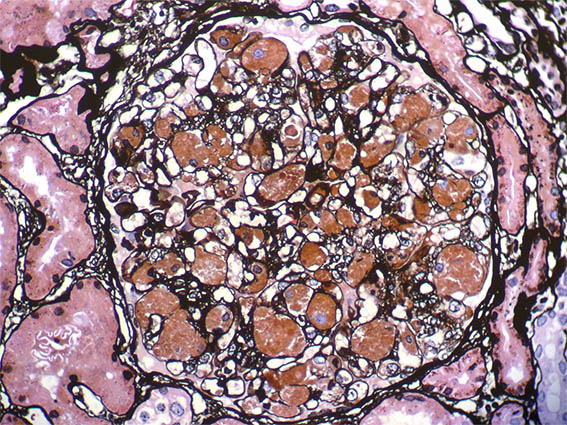

Figura 5. Plata-metenamina, X400.

Figura 6. Plata-metenamina, X400.